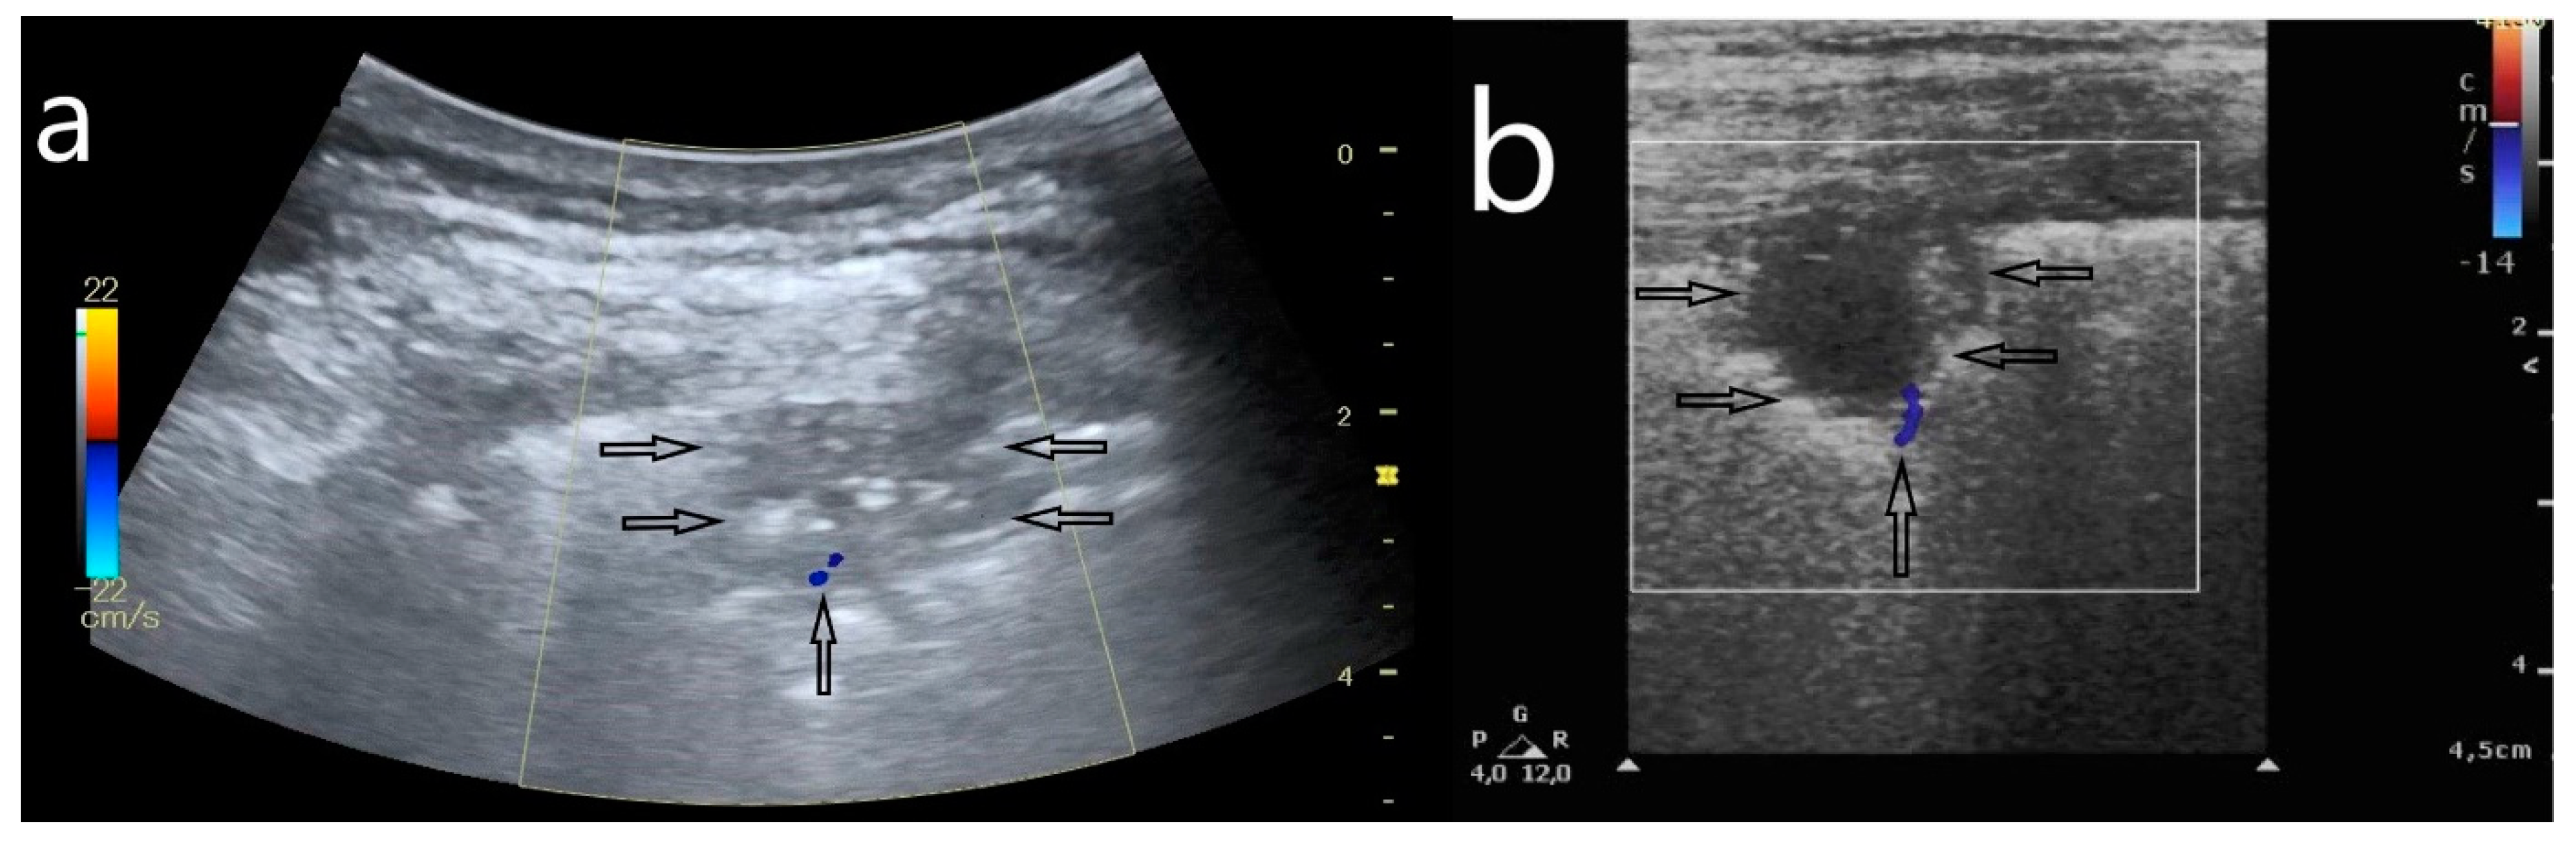

- Consolidations: small subpleural consolidations (up to 5 mm) accompanied with C-line artifacts, large consolidations involving segments and/or lobes, pleural effusion.

- Large consolidations involving segments and/or lobes;

- Pleural effusions.

- Large consolidations involving segments or lobes in an HRCT scan and large consolidations in an LUS image (p = 0.007).